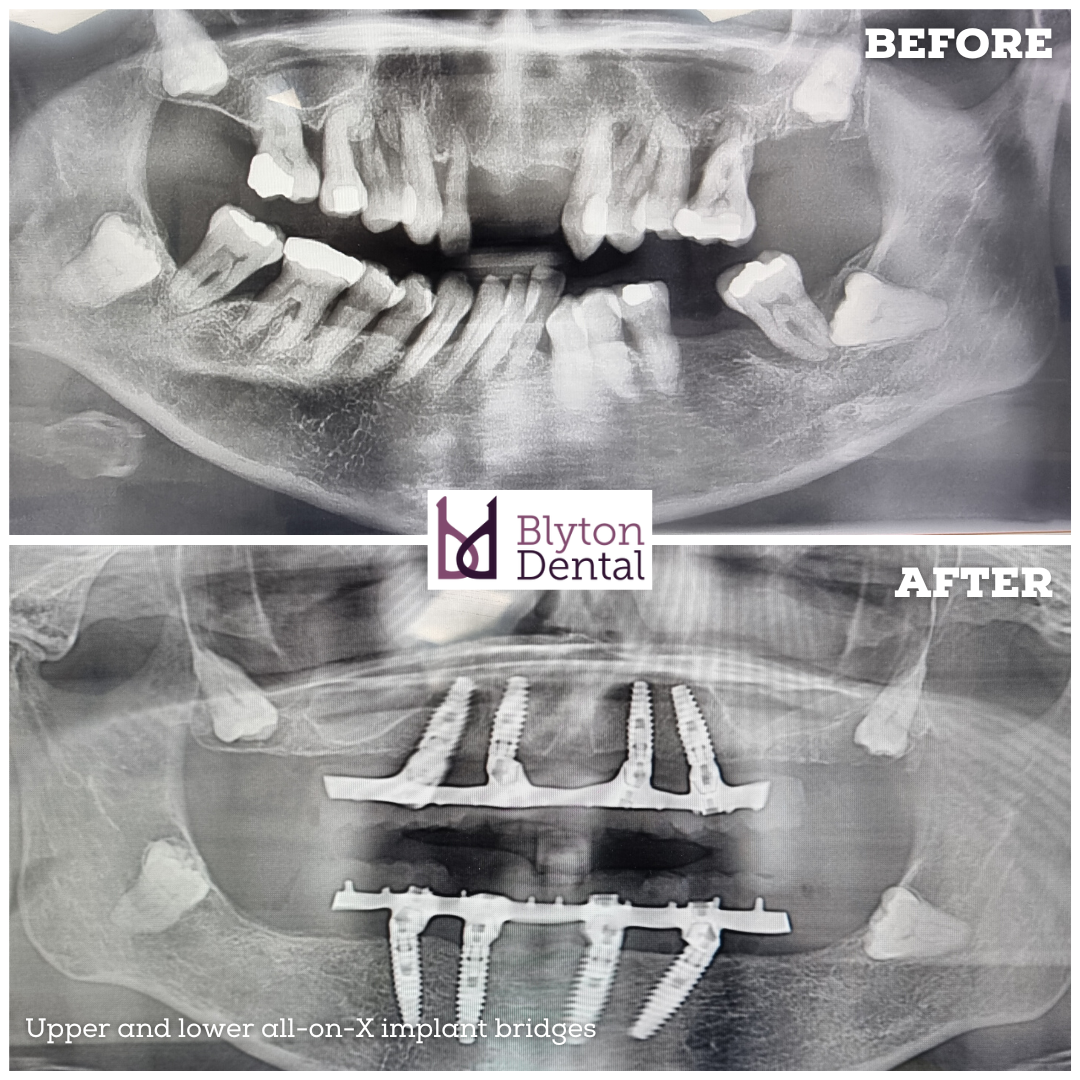

This lady was unfortunate to lose all her remaining teeth due to very bad periodontal disease and she could not get used to her dentures, so we replaced them with implant supported hybrid bridges.

All on X/same-day teeth/teeth express can be a great option for someone with terminal dentition to improve the function and appearance.